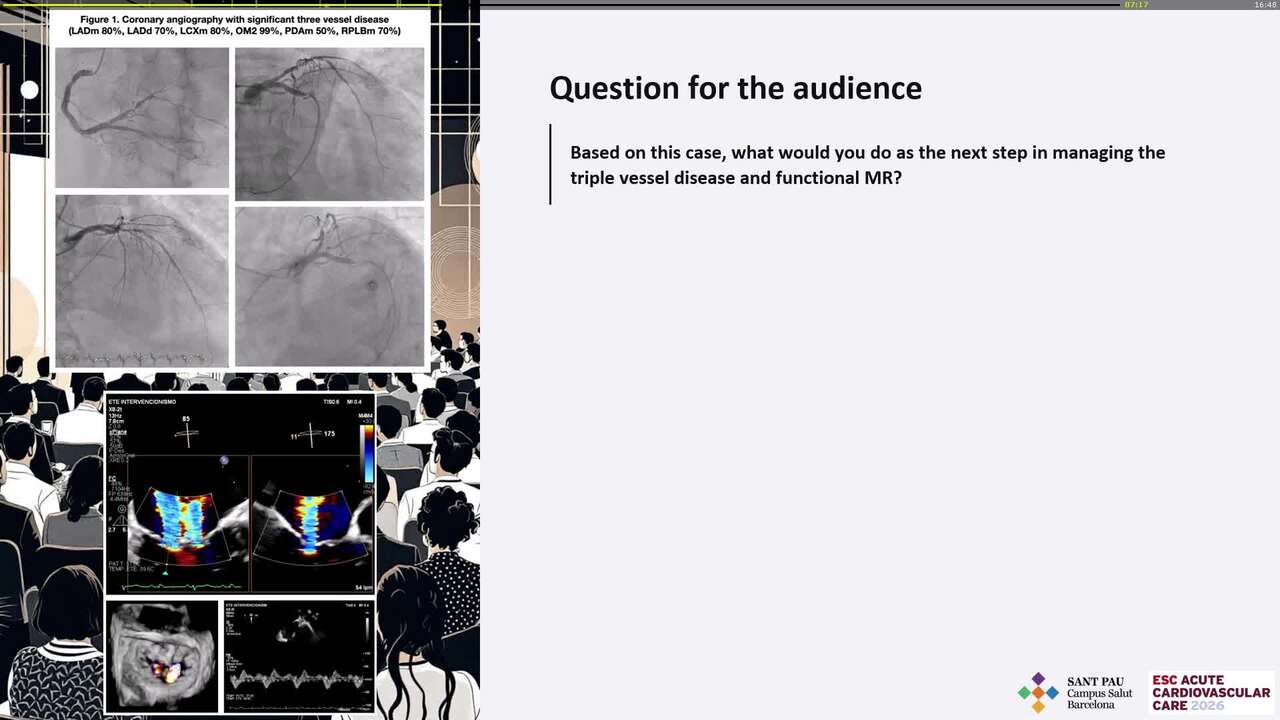

Rescue TTVR with a new-sized EVOQUE valve following transcatheter edge-to-edge repair